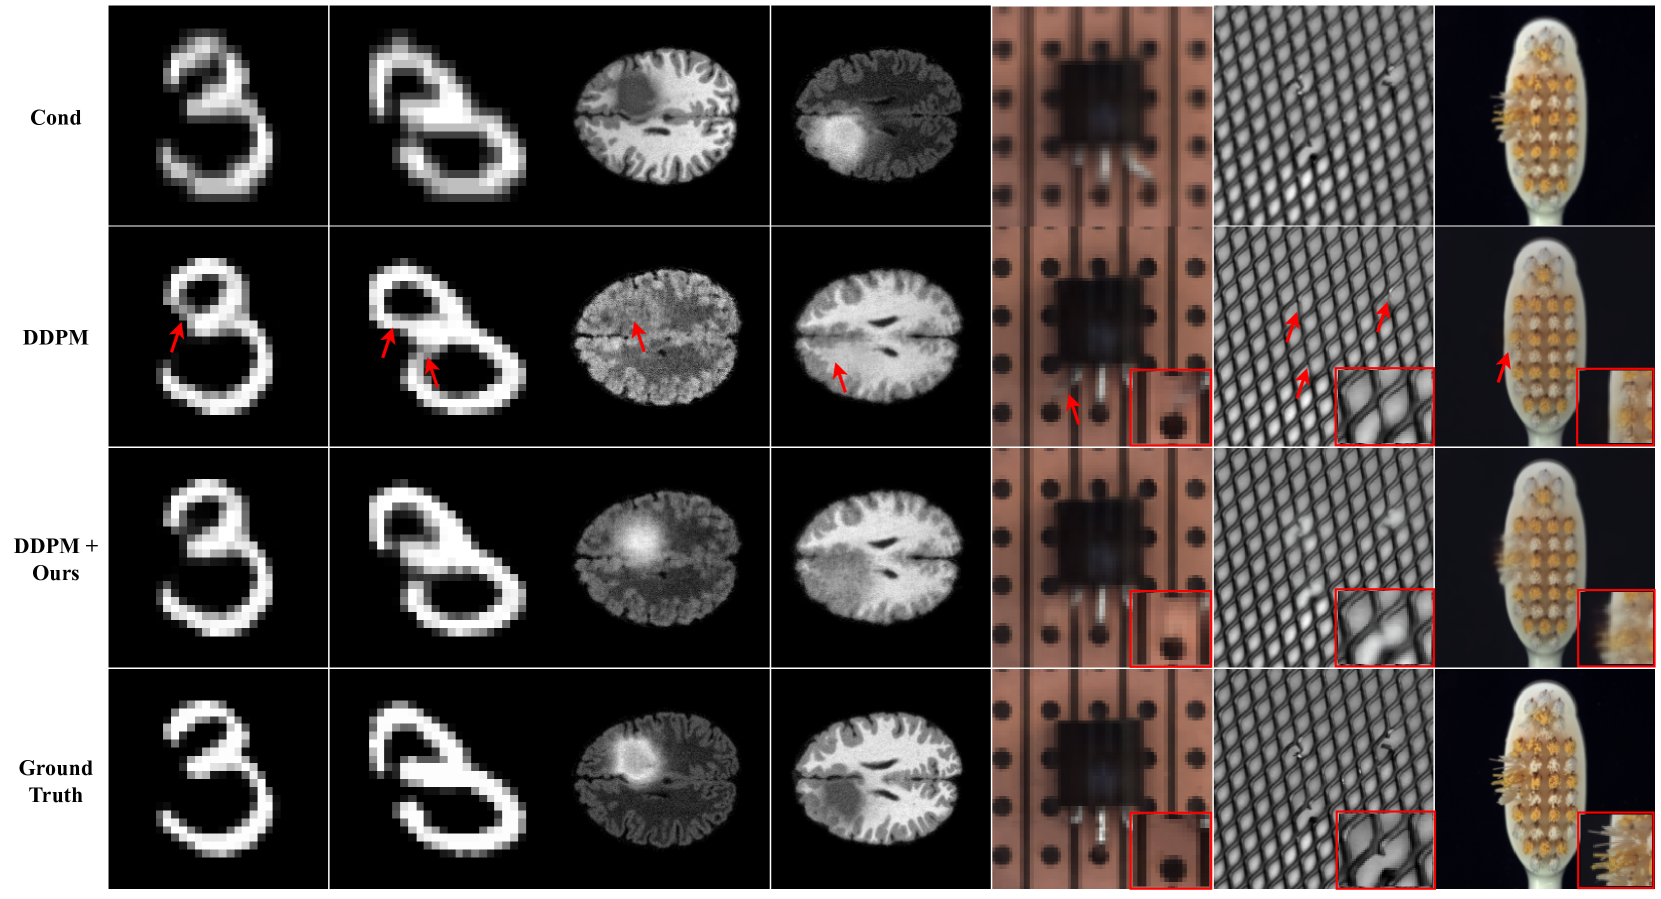

Fig 6 presents a qualitative comparison against DDPM[10], showcasing the effectiveness of our proposed method in reducing structural hallucinations. In the BraTS, predictions generated using DDPM[10] contain hallucinated features, notably misidentifying tumor tissues as healthy white matter. In contrast, our method accurately delineates tumors with appropriate intensity ranges. While the MNIST and BraTS feature relatively large OOD areas, the MVTec dataset comprises different types of OOD with various sizes (e.g., broken leads or grids), posing a challenge for hallucination mitigation. Despite these challenges, our approach demonstrates robust performance on various OOD types, as shown in Fig 6, affirming its effectiveness on various image modalities.

Refer to caption

Figure 6: Qualitative comparison on MNIST, BraTS and MVTec (From top: condition, DDPM[10], DDPM with ours and ground truth). The red arrows indicate structural hallucination.